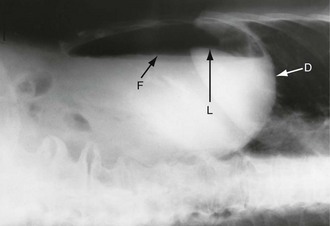

Free intraperitoneal gas: Free gas is diagnostic of bowel perforation except after recent laparotomy. A horizontal beam chest or upper abdominal X-ray with the patient erect is the most useful method of demonstrating it as a radiolucent layer beneath the diaphragm (see Fig. 19.8, p. 275). The layer can be very small but is often obvious. Perforation can also be confidently diagnosed when the inside and outside of the bowel wall are both outlined by radiolucent shadows, but this is rare (Rigler's sign, Fig. 32.7, p. 413). Where the result is doubtful or the patient too ill to sit or stand, he or she should be placed in the right-side raised lateral decubitus position (i.e. lying on the left side) for 10 minutes. A horizontal beam X-ray taken across the table can then reveal as little as 2 ml of gas above the lateral liver border (Fig. 5.4).